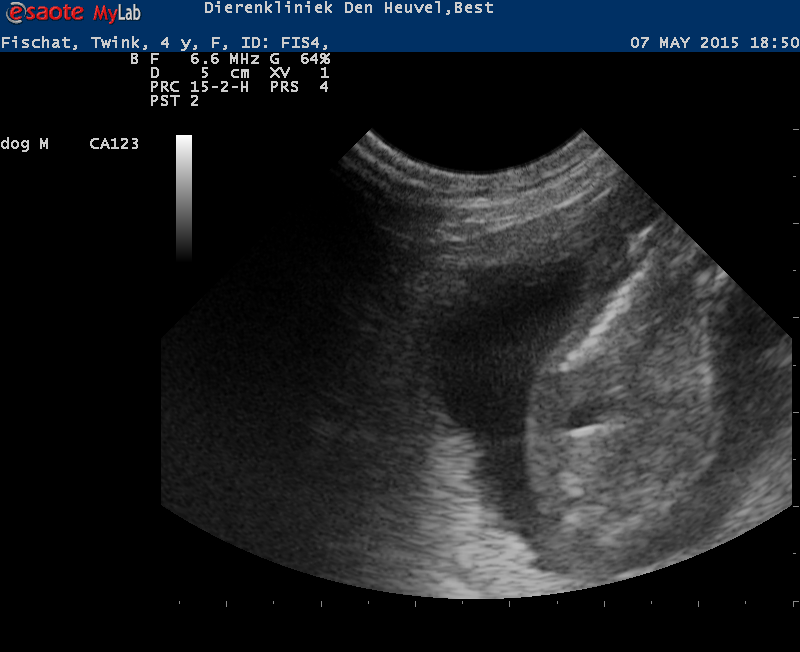

Wat een verdrietige tijdperk was, was er toch een klein lichtpuntje! Op de echo was te zien dat Bridget drachtig is en eind juli 2025 mogen we na 3 jaar eindelijk weer eens een nestje verwachten. Zo zie je maar weer dat het leven heel wisselvallig kan zijn en leven en dood zit heel dicht bij elkaar. Wij zijn dan ook reuze benieuwd naar de pups en nieuw leven!

Wij hadden al een tijdje een vermoeden, maar de echo heeft het bevestigd…. Wies is drachtig! Als alles goed gaat, verwachten wij in de eerste week van juni de puppies.